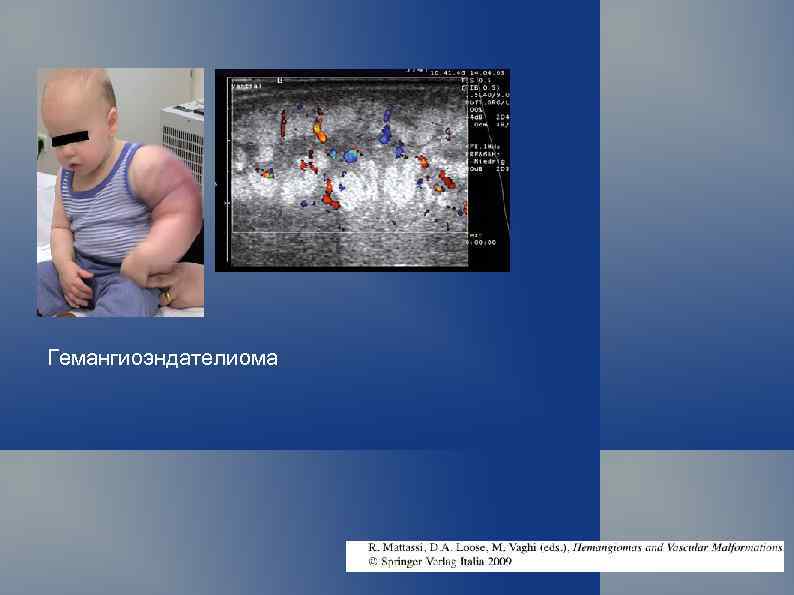

Гемангиоэндателиома